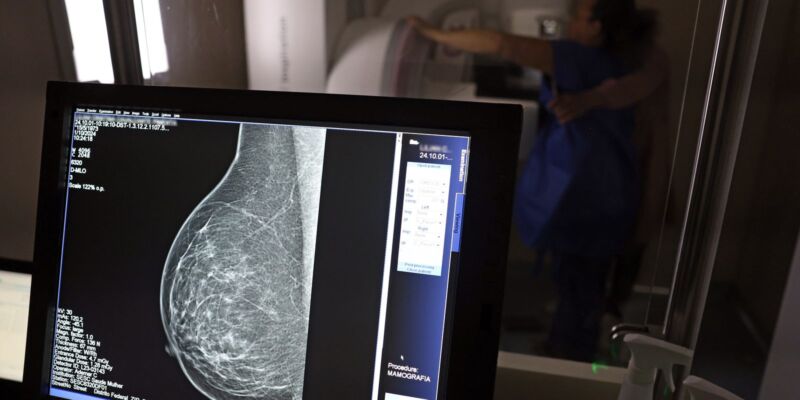

No mês de conscientização sobre o câncer de mama, um relatório destaca a importância de acesso igualitário ao rastreamento e tratamento da doença. Segundo o Atlas da Radiologia no Brasil, do Colégio Brasileiro de Radiologia e Diagnóstico por Imagem (CBR), o acesso aos mamógrafos ainda é um desafio.

O país tem 6.826 equipamentos registrados, sendo 96% em funcionamento. Metade deles está disponível no Sistema Único de Saúde (SUS), responsável por atender 75% da população. Isso equivale a 2,13 mamógrafos por 100 mil habitantes dependentes do SUS.

Na saúde suplementar, que cobre 25% da população, o cenário é mais favorável: 6,54 aparelhos por 100 mil beneficiárias, quase o triplo da rede pública. O Acre exemplifica essa disparidade — são 35,38 mamógrafos por 100 mil habitantes na rede privada, contra 0,84 no SUS.

O Brasil tem uma cobertura muito baixa de mamografias: 24%. O ideal recomendado pela Organização Mundial da Saúde é de 70%. Mesmo em lugares como o estado de São Paulo, que tem a maior concentração de mamógrafos do país, a taxa gira em torno de 26%.

Em setembro, o Ministério da Saúde ampliou as diretrizes de rastreamento, recomendando que mulheres entre 40 e 49 anos realizem mamografias, mesmo sem sintomas. De acordo com o Instituto Nacional do Câncer (Imca), mais de 73 mil mulheres recebem o diagnóstico de câncer de mama anualmente no Brasil.

“O que é efetivo na redução da mortalidade é você descobrir o tumor antes de ter sintoma clínico. Quanto menor o tumor, melhor para a gente descobrir o tratamento e maior a chance de cura. E a gente só consegue fazer isso com exames de imagem”, diz Ivie.

Ela explica que no caso de diagnóstico de um câncer de mama com menos de 1 cm, a chance de cura é de 95% em cinco anos, independentemente se ele é do tipo mais agressivo. “E esses tumores só vão ser detectados na mamografia. Essas pessoas que têm que ir fazer mamografia são mulheres saudáveis. Não são mulheres doentes”, acrescenta.